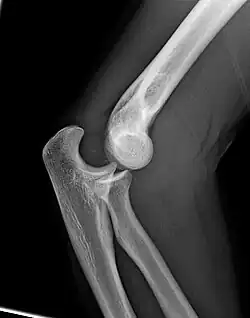

Left: Lateral X ray of a dislocated right elbow

Right: AP X ray of a dislocated right elbow

The types of disease most commonly seen at the elbow are due to injury.

X-ray of ventral dislocation of the radial head. There is calcification of annular ligament, which can be seen as early as 2 weeks after injury.[29]

Elbow dislocations constitute 10% to 25% of all injuries to the elbow. The elbow is one of the most commonly dislocated joints in the body, with an average annual incidence of acute dislocation of 6 per 100,000 persons.[30] Among injuries to the upper extremity, dislocation of the elbow is second only to a dislocated shoulder. A full dislocation of the elbow will require expert medical attention to re-align, and recovery can take approximately 6 weeks.